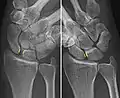

Scapholunate ligament disruption associated with a Colles' fracture